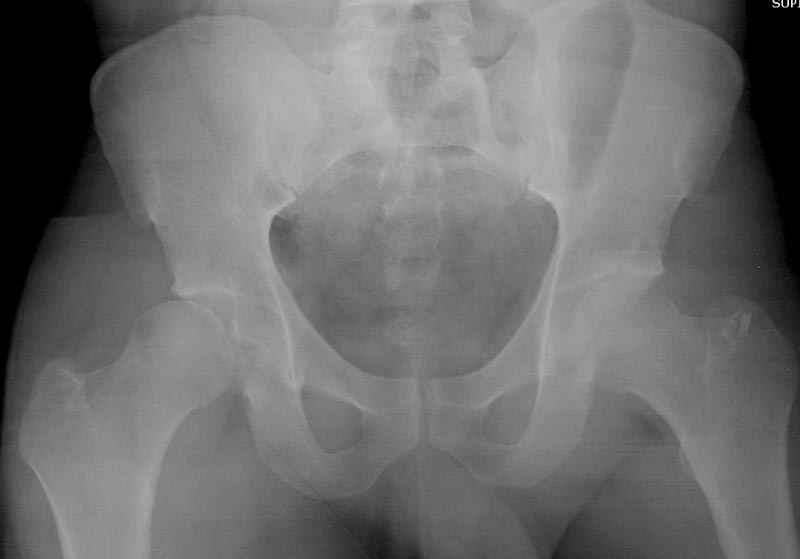

5:24 Рентгенограмма таза, вызывают врача ортопеда (снимок N1), его диагноз: закрытый переломо-вывих правого тазабедренного сустава, получает добро на закрытую репозицию в приемном отделении

5:38 Дважды неудачная попытка закрытой репозиции в приемном отделении

N 2

6:20 ответстенный врач принимает решение о репозиции в условиях операционной, предупреждаются родственники и больной, что при неудачной закрытой репозиции, о возможности открытой репозиции и фиксации задней стенки вертлужной впадины.

7:30 начало операции, больной на спине, попытка репозиции после анестезии N3, укладка больного на боку, доступ Kocher- Langenbeck, состояние седалищнего нерва около 2.5см кровоподтек, через joistick головка бедра приподнята, освобовождение сустава, фрагмент заднего края более 3х4 см репонирован на свое место. После промывания

сустава, репозиция вывиха (N4), фиксация фрагмента 2.7(4) мм шурупами и допольнительно реконструктивной пластиной на 8 дырок, фиксация 3.5мм шурупами проксимально и дистально.

Интраоперционные N5 косая запирательная и N6 подвздошный снимок

11:50 больной в послеоперационной, рентгенограмма N7, компьютерная томограмма в тот же день N8-10